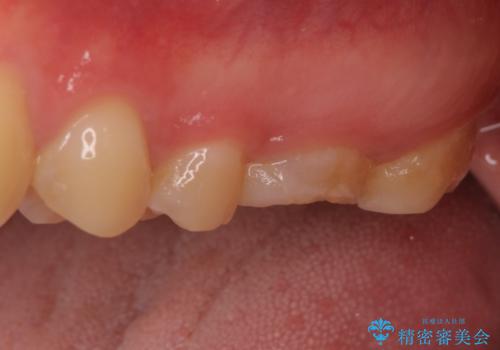

- ラバーダムや顕微鏡を用いた根管治療を希望されて、転院された患者様です。

前医にて神経を取り除いた処置を行った際、ラバーダムが使用されなかったとのことで転院されてきました。

根管治療を実施した後、フルジルコニアクラウンに補綴することとしました。